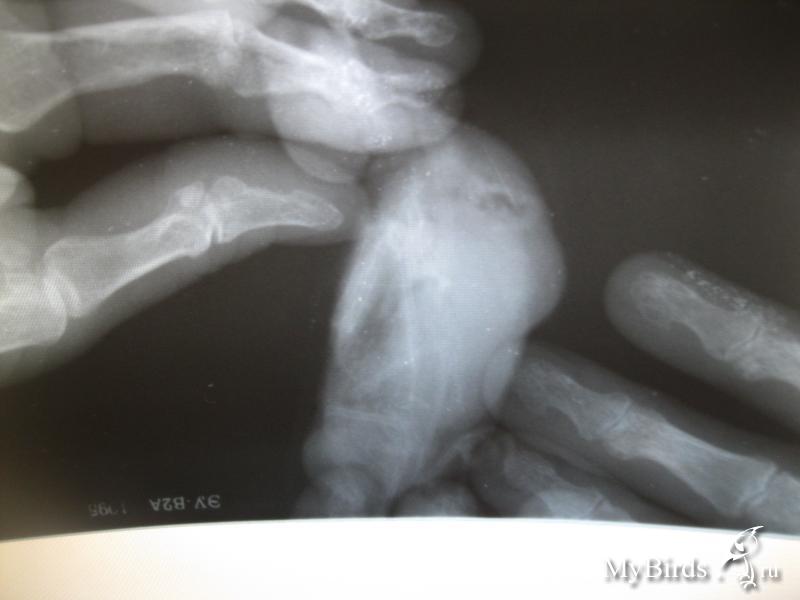

Посоветуйте, пожалуйста, как лечить птичку. Вы последняя надежда. Снимок липомы прикрепила.

post-66918-1467025972_thumb.jpg

2.На фото липома, вроде простая (не "матрешка", но рентген нужен).

Не очень качественные снимки:

post-66918-1468911105_thumb.jpg

post-66918-1468911147_thumb.jpg